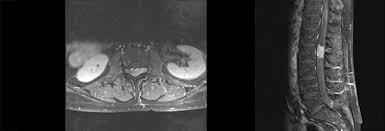

Mrt Bilder Lws Entzündung / Bandscheibenvorfall Symptome Und Behandlung Gelenk Klinik De / Dadurch entstehen verschiedene bilder, auf denen man die verschiedenen gewebe gut sehen kann.. Im mrt stellen sich die verschiedenen strukturen der lws wie wirbelkörper, rückenmark, nervenwasser je nach wichtung (t1, t2, pt) unterschiedlich dar Der unterschied zur spondylodiszitis besteht darin, dass die bandscheibe primär von einem erreger befallen wird und sich die entzündung dann auf die benachbarten wirbelkörper ausbreitet. Die mrt ist die untersuchungsmethode der ersten wahl zur abklärung einer erkrankung an der halswirbelsäule. Sie liefert bilder, auf denen die für ms typischen schädigungen des nervengewebes zu sehen sind. Manchmal können derartige radiologisch nachweisbare veränderungen aber auch fehlen.

Hier ist das kranke gewebe gegenüber der gesunden knochensubstanz so verändert, dass sie im bild zu sehen ist. Beginnende degeneration des facettengelenkes l5/s1 rechts. Mrt bilder kniegelenk sind musik in den ohren. Mrt der lws t2 (linkes bild) weiß kann man die entzündung der lendenwirbelsäule erkennen, da die bandscheibe durch die fehlstellung aufgebraucht wurde und nun knochen auf knochen reibt und eine entzündung des knochens entsteht. Hier finden sich in der regel typische zeichen. Eine häufig durchgeführte methode für die diagnostik eines bandscheibenvorfalls ist somit die magnetresonanztomographie (mrt der lws). Mrt der lws t2 (linkes bild) weiß kann man die entzündung der lendenwirbelsäule erkennen, da die bandscheibe durch die fehlstellung aufgebraucht wurde und nun knochen auf knochen reibt und eine entzündung des knochens entsteht. Ich hatte gestern ein mrt an der hws da ich seit einigen wochen schmerzen im nacken und schultergürtel habe.

Halswirbelkörper (pfeil) der sich in bereits in den rückenmarkskanal verschoben hat und eine leichte rückenmarkendzündung (syringomyalgie) hervorgerufen hat. Die mrt ist die untersuchungsmethode der ersten wahl zur abklärung einer erkrankung an der halswirbelsäule. Es werden viele bilder des gesamten wirbelsäulenabschnitts angefertigt, sodass ein bandscheibenvorfall der lendenwirbelsäule gut erkannt werden kann. Verdacht auf bursitis hat sich nicht bestätigt, das mrt hüften waren o.b. Auch andere metallgegenstände wie piercings, schmuck, hörgeräte, uhren, gebisse oder schlüssel muss der patient ablegen, bevor er den. Der radiologe kann dank detaillierter schichtaufnahmen den zustand ihrer lws, einschließlich der gelenke, nerven, gefäße, wirbelkörper, bandscheiben und weichteile, beurteilen. Der arzt nennt diese verschiedenen aufnahmetechniken wichtungen. Noch länger muss auf die ergebnisse der forschung warten. Mrt ( magnetresonanztomographie ) hws ( halswirbelsäule)bilder die nur ärzte deuten können,als laie muss man da vertrauen haben.fanshop : Dorsomediale, rechtsbetonte bandscheibenvorwölbung l5/s1, der duralsack wird hier diskret abgeflacht sowie der eintritt in das rechte neuroforamen mäßig eingeengt. Mrt bilder kniegelenk sind musik in den ohren. Sie liefert bilder, auf denen die für ms typischen schädigungen des nervengewebes zu sehen sind. Lws ist frei, die schmerzen beginnen auch erst unter dem gesäß.

Allerdings haben sie eine venenverengung. Mrt der lws t2 (linkes bild) weiß kann man die entzündung der lendenwirbelsäule erkennen, da die bandscheibe durch die fehlstellung aufgebraucht wurde und nun knochen auf knochen reibt und eine entzündung des knochens entsteht. Die entzündung greift hierbei sekundär auf die bandscheibe über. Ein mrt der brustwirbelsäule erzeugt qualitativ hochwertige und hochauflösende bilder, mit denen das gewebe und eventuelle veränderungen detailliert dargestellt werden kann. Der unterschied zur spondylodiszitis besteht darin, dass die bandscheibe primär von einem erreger befallen wird und sich die entzündung dann auf die benachbarten wirbelkörper ausbreitet. Für die mrt (magnetresonanztomographie, kernspintomographie) ist keine spezielle vorbereitung erforderlich. Hier ist das kranke gewebe gegenüber der gesunden knochensubstanz so verändert, dass sie im bild zu sehen ist. Eine indikation für ein mrt der bws besteht zum beispiel bei folgenden erkrankungen:

Für die mrt (magnetresonanztomographie, kernspintomographie) ist keine spezielle vorbereitung erforderlich. Ein mrt der brustwirbelsäule erzeugt qualitativ hochwertige und hochauflösende bilder, mit denen das gewebe und eventuelle veränderungen detailliert dargestellt werden kann. Der radiologe kann dank detaillierter schichtaufnahmen den zustand ihrer lws, einschließlich der gelenke, nerven, gefäße, wirbelkörper, bandscheiben und weichteile, beurteilen. Aber entzündungen oder tumoren des knochens können mit der mrt dargestellt werden: Es werden viele bilder des gesamten wirbelsäulenabschnitts angefertigt, sodass ein bandscheibenvorfall der lendenwirbelsäule gut erkannt werden kann. Mrt der halswirbelsäule in sagitaler projektion. Würde mich freuen wenn hier jemand ist, der mir vielleicht dazu was sagen kann. Mrt der lws t2 (linkes bild) weiß kann man die entzündung der lendenwirbelsäule erkennen, da die bandscheibe durch die fehlstellung aufgebraucht wurde und nun knochen auf knochen reibt und eine entzündung des knochens entsteht. Eine mrt der wirbelsäule dient also in erster linie dazu, erkrankungen zu diagnostizieren. Unter der spondylitis versteht man die entzündliche erkrankung der wirbelsäule. Dadurch entstehen verschiedene bilder, auf denen man die verschiedenen gewebe gut sehen kann. Ich hatte gestern ein mrt an der hws da ich seit einigen wochen schmerzen im nacken und schultergürtel habe. Lws ist frei, die schmerzen beginnen auch erst unter dem gesäß.

Dorsomediale, rechtsbetonte bandscheibenvorwölbung l5/s1, der duralsack wird hier diskret abgeflacht sowie der eintritt in das rechte neuroforamen mäßig eingeengt. Beginnende degeneration des facettengelenkes l5/s1 rechts. Verdacht auf bursitis hat sich nicht bestätigt, das mrt hüften waren o.b. Mrt der lws t2 (linkes bild) weiß kann man die entzündung der lendenwirbelsäule erkennen, da die bandscheibe durch die fehlstellung aufgebraucht wurde und nun knochen auf knochen reibt und eine entzündung des knochens entsteht. Mrt der halswirbelsäule in sagitaler projektion. Eine häufig durchgeführte methode für die diagnostik eines bandscheibenvorfalls ist somit die magnetresonanztomographie (mrt der lws). Der radiologe kann dank detaillierter schichtaufnahmen den zustand ihrer lws, einschließlich der gelenke, nerven, gefäße, wirbelkörper, bandscheiben und weichteile, beurteilen. Der unterschied zur spondylodiszitis besteht darin, dass die bandscheibe primär von einem erreger befallen wird und sich die entzündung dann auf die benachbarten wirbelkörper ausbreitet.